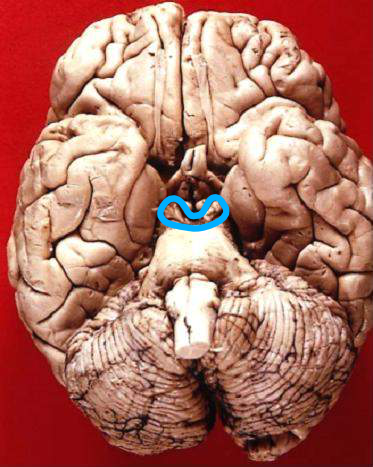

শব্দ ও ভাষা সম্বন্ধীয় তথ্যের সময়গত উপাংশগুলি প্রথমে “সুপিরিয়র টেম্পোরাল সালকাস”-এ সময়ের ভিত্তিতে ও তারপর “অ্যাসোসিয়েটিভ অডিটারি কর্টেক্স”-এ কম্পাঙ্কের ভিত্তিতে এনকোডেড্ হওয়ার পর “ভিসুয়াল কর্টেক্স”-এ আসে। আবার “সুপিরিয়র টেম্পোরাল সালকাস”-র পলিসেন্সরি অংশটি দৃষ্টি সম্বন্ধীয় তথ্যের সময়গত উপাংশগুলিকে এনকোড্ করে ভিসুয়াল কর্টেক্স-এ পাঠায়। ভিসুয়াল কর্টেক্স এই সকল এনকোডেড্ তথ্যকে সার্চ ক্রাইটেরিয়া হিসাবে ব্যবহার করে প্রোসিডিউরাল লং টার্ম মেমোরি (পদ্ধতিগত দীর্ঘ মেয়াদী স্মৃতি)-তে এনকোডেড্ অবস্থায় সঞ্চিত বিভিন্ন অর্জিত দক্ষতা (স্কিল) বা করণীয় কাজ (টাস্ক) সম্বন্ধীয় তথ্যগুলির মধ্য থেকে কিছু তথ্য রিট্রিভ করে তাদেরকে ডিকোড্ করে – মস্তিষ্কের এই কার্য সম্পাদন করার ক্ষমতাই “স্বজ্ঞা”(ইন্টিউয়েশন্)-র পরিচায়ক। আর রিট্রিভ করা এই এনকোডেড্ তথ্যগুলিকে ডিকোড্ করার পর তাদেরকে কাজে লাগানোর জন্য ভিসুয়াল কর্টেক্স যদি পুনরায় তাদেরকে এনক্রিপ্ট করে, সেই প্রক্রিয়াকেই “কল্পনা”(ইম্যাজিনেশন্) বলে।